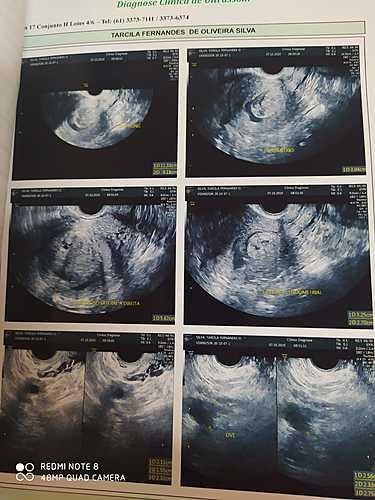

Oi pessoal, me chamo Tarcila, tenho 41 anos, moro em Águas Lindas de Goiás. Infelizmente me encontro em um momento ruim, recentemente precisei ser internada por 6 dias, por causa de intensos sangramentos causados por dois miomas no útero, com isso, também desenvolvi uma forte anemia. Nesse cenário, a decisão médica é a de que eu opere o quanto antes, afinal, estou com sangramentos há mais de 30 dias, apesar dos remédio, não é possível interromper o sangue, apenar contornar um pouco, fora as dores continuas.